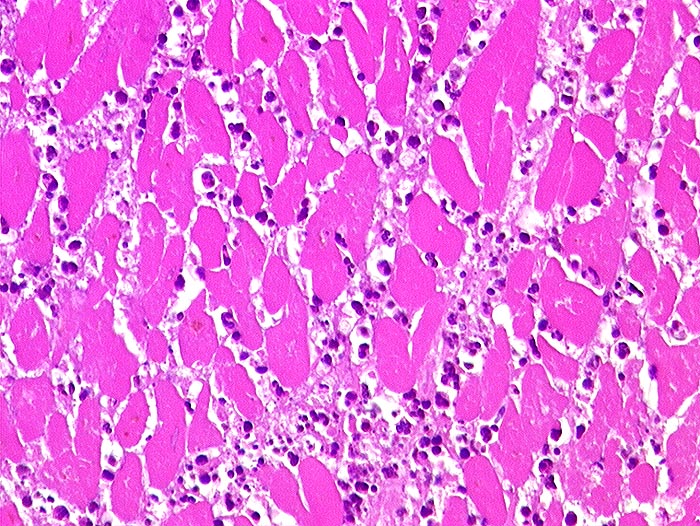

PathoPic – image database / PathoPic ID 140 - akuter Myokardinfarkt

akuter Myokardinfarkt

Die Myozyten sind schollig zerfallen und hypereosinophil, Kernstrukturen sind nicht mehr erkennbar. Zwischen den nekrotischen Muskelfasern dichte granulozytäre Entzündungsinfiltrate.

akuter embolischer Myokardinfarkt bei Aortenklappenendokarditis.